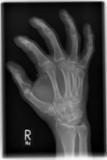

Rheumatoid arthritis with incipient erosive destruction

Those who have looked closely will have already recognized the erosion in the head of the third metacarpal bone on the X-ray image. This is shown here only as a faint cysitic lesion without a clear interruption of the cortex. The oblique projection was very helpful here. Unfortunately, these are rarely done anymore.